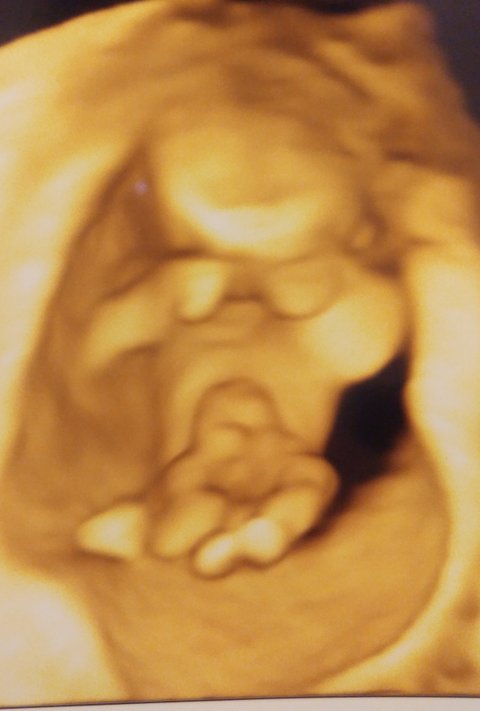

애기 성별구별좀 해주세요!!

괌가기전에 성별을 알아보구 애기옷사려고하는데

핑쿠일까요 블루일까요!?